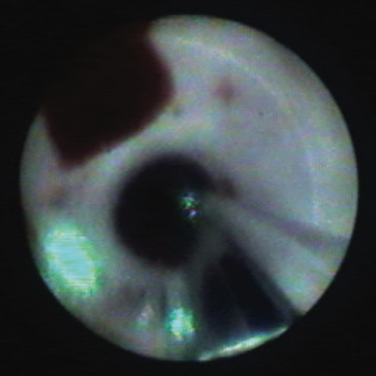

The balloon was inflated in the RIPV. Upon inflation, it was observed that the balloon had cannulated the lower branch of the RIPV and that the antrum of the upper branch was not fully exposed (Figure 1). To expose the large superior branch of the RIPV, the balloon size was adjusted to the optimal size and the sheath was lifted, tilting the balloon up until both large branches were fully exposed (Figure 2). Thirteen watts of RAPID energy were delivered around the antrum. The more narrow superior carina section required a few manual lesions at 5.5W. A total of 317 seconds of therapy time was delivered and 62% of the ablation time was in RAPID mode.

The X3 catheter is the newest FDA-approved system from CardioFocus and is indicated for the treatment of drug refractory recurrent symptomatic paroxysmal atrial fibrillation. The biggest advancement is the introduction of a motor into the balloon catheter handle to enable continuous energy delivery in a user-controlled arc similar to “drag and burn” ablation, in addition to point-by-point RF applications. The pear-shaped balloon’s size can be adjusted from approximately 7 mm up to 40 mm to conform to a wide variety of pulmonary vein (PV) anatomies via a compliant balloon delivered to the left atrium (LA) through a 12 French (Fr) deflectable sheath. Real-time visualization is achieved via a 2 Fr endoscope, which sits in the central shaft. The endoscope is seated on one side of the central catheter shaft, and as a result, the view of the PV ostium is approximately 300° at any given time.

The laser balloon is filled with deuterium oxide or heavy water and contrast media, which allows for fluoroscopic visualization, cooling of the balloon, and full transmission of the infrared laser energy onto the tissue. A unique feature of the infrared energy is that it passes through the endothelial lining and is absorbed by the myocardium. The maneuverable optical fiber generates a ~30° arc/spot of both non-ablative visible light and near-infrared ablative light energy. The aiming beam of light can be advanced, retracted, and rotated to project to anywhere on the surface of the balloon. The balloon catheter has a soft and flexible tip segment, which provides visual contact feedback. Just proximal to the balloon is a radiopaque “Z” marker that can be seen on fluoroscopy to properly align the endoscopic image in a consistent superior at the top and inferior at the bottom orientation.